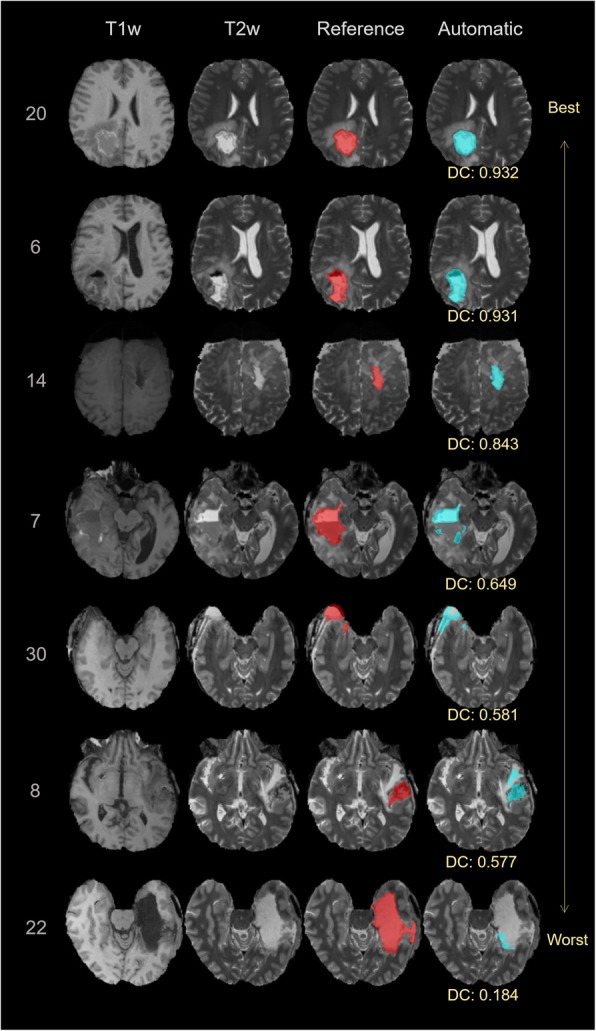

Fig. 4.

Representative axial slices of the produced segmentations in comparison to the expert consensus. The rows correspond to different cases and are listed according to the segmentation performance in terms of Dice coefficient (DC). The columns show the T1-weighted (T1w) image, the T2-weighted (T2w) image, the expert consensus (reference) and the automatic segmentation (as overlay on the T2w)

The DC and the relative volume error of the different pairings of expert raters and the automatic segmentation are listed in Table 2. The median overall DC among the raters was 0.85 (interquartile range [IQR]:0.07). The median DC between the automatic segmented RCs and the fused reference segmentation was 0.84 (IQR: 0.10), and slightly lower than the agreement among raters. In terms of relative volume error, we found a median error of − 13.17%, (IQR: 24.17%) between automatic and reference segmentations, which indicates the DL method underestimated the RC with respect to the raters. The median of the absolute volume was 24.7cm3 (IQR: 19.1cm3) for EE, 26.6cm3 (IQR: 26.7cm3) for EH, 26.1cm3 (IQR: 23.3cm3) for MB and 21.7cm3 (IQR: 19.6cm3) for the automatic segmentation. Figure 2 shows boxplots of DC values, relative volume errors and the absolute volumes for the automatic approach in relation to the experts. According to the Kruskal Wallis test we did not detect a statistically significant difference regarding the distribution of the measured volumes for the different raters and the automatic method (chi-square = 1.46, p = 0.69). In contrast, a statistically significant difference in DC (chi-square = 11.63, p = 0.04) and relative volume error (chi-square = 22.45, p = 0.00043) was found. The result of the subsequent Wilcoxon rank-sum test between rater-to-rater (EE-EH, EE-MB, EH-MB) and automatic-to-rater (Automatic-EE, Automatic-EH, Automatic-MB) pools are shown in Figs. 2 and 3. The automatic segmentation volumes tend to be smaller than the expert volumes, which corresponds with the underestimation found in the relative volume error measurement. The main sources of error by the automatic method were localized to signal inhomogeneity (especially in T2w and FLAIR sequences) and other intensity patterns (edema, subarachnoid space, or ventricles). Figure 4 shows cases representing good and bad performances.

Although the results are promising, the auto-segmentation is characterized by some typical errors. The observed lower overall volume of the automated approach with respect to the volume of the reference segmentation seems to be mostly caused by specific outlier cases 7, 22 and 23 (Figs. 3 and 4). The divergent results in the outliers are due to a deficiency of the model to identify blood products, air pockets and other deviating MRI intensities, which result in image areas not being included in the RC. Figure 5 illustrates clearly how the automatic segmentation excludes air and blood from the RC. Within the cohort of 30 cases, the occurrence of air pockets and or blood products in the RC were to scarce for proper DL training. A larger cohort and better characterizing these confounding effects, can enable an effective stratification of blood products and air pockets, and lead to improved capability of handling these cases. The small retrospective dataset used for this proof of concept study is also a limitation because it can result in bias in the selected cases. It is a monocentric study and the images are obtained from only two MRI scanners. To obtain a more general validation, a larger prospective multi-institutional dataset is required to confirm the current preliminary results.